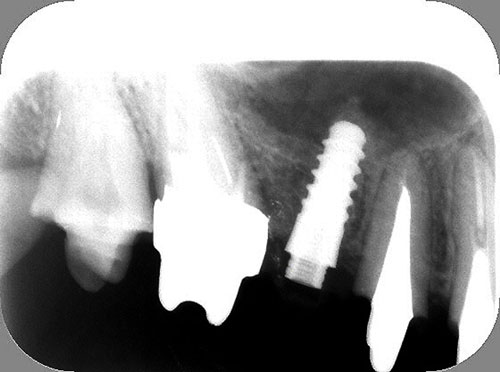

Mientras dichos movimientos ortopédicos se producen (período que supondrá otros seis meses), estudiamos los actos quirúrgicos a realizar en los cuatro implantes que pondremos. De acuerdo al estudio Desatascan realizado observamos tres situaciones diferentes: 1º-El Primer Molar Inferior Izquierdo, lo instalamos mediante Cirugía Minimamente Invasiva , con la aplicación de una Férula Quirúrgica Obtenida de los datos del scanner tratados con un programa de CMI (Cirugía Minimamente Invasiva), previa prueba en un modelo estereolitográfico, ya que la altura ósea era apenas de 9 mm. 2º- El Primer Molar Superior Derecho, se implantará mediante una ligera Elevación Atraumática (Trans alveolar) de Seno una vez logrado el espacio mesio distal necesario. 3º- El Incisivo Central Superior Derecho ausente, cuenta con un sustrato óseo prácticamente inexistente. El espesor de la tabla era de menos de 2 mm. Los caminos posibles a seguir para contar con una Rehabilitación de piezas independientes son dos: Optamos por esta segunda opción por ser menos cruenta y no necesitar de una zona dadora. Técnica esta que pondremos en práctica en dos etapas diferidas: 1º-Incisión horizontal palatinizada, incisiones peri rodetes gingivales e incisiones de descarga. Dilatación que comenzamos con dos incisiones de descarga sobre la cortical vestibular realizadas con disco. y el comienzo de la dilatación propiamente dicha mediante una hoja de bisturí, para luego seguir con un periostótomo . Recién después de alcanzada una cierta separación de la cortical vestibular de la palatina, empezamos con los dilatadores roscados. En este punto podríamos haber utilizado sin riesgos un Implante de 3,8 mm de diámetro, pero a fin de mejorar la estética del pilar emergente decidimos rellenar con material osteoconductor y osteoinductor (BiOss) y cubrir mediante membrana reabsorvible ( Bio Guide). 2º-Implantación seis meses después. Mientras se van cumpliendo los tiempos antes mencionados, y comprobamos reiteradamente la funcionalidad de la oclusión con los provisorios, tomamos impresiones definitivas y construimos primero el maxilar inferior, para definir en primer término la porción inferior de la Guía Anterior., y a nivel posterior Curvas y Microplanos. Para luego realizar los cuadrantes premolar- molar del superior: La espera de la regeneración ósea y sus tiempos pertinentes, más la espera de los tiempos de la implantación, nos obligaron a modificar las etapas del protocolo D.AT.O de manera de mantener la –D- mediante el sector superior de la GA. en provisorios, mientras fuimos resolviendo en forma definitiva los demás sectores. Ya pasados los meses necesarios para recrear un hueso adecuado en el área del Incisivo Superior Derecho, procedemos a resolver la implantación de dicha zona, observando que todo el esfuerzo dedicado al mismo había sido inútil, ya que la formación de hueso se produjo minimamente. Cuatro meses después tomamos impresiones del sector Antero Superior de la Guía Anterior, incluyendo el arrastre de un transfer . Seguimos modelando la encía con un nuevo juego de provisorios. Y se construye entonces el sector superior de la Guía Anterior. Se efectúa un control radiográfico a los 6 meses. Se ha intentado mostrar en esta Rehabilitación, que a pesar de las distintas circunstancias de cada paciente, siempre debemos tener en cuenta la necesidad de ejercer la DESOCLUSIÓN del caso como prioridad número uno, para luego perseguir la ALINEACIÓN TRIDIMENSIONAL de las arcadas y obtener así una OCLUSIÓN equilibrada. D.AT.O. ES EL PROTOCOLO QUE DEBEMOS SEGUIR EN TODA REHABILITACIÓN. BIBLIOGRAFÍA 1)William Mc Horris,B.S.,D.D.S. Oclusión. Con especial énfasis sobre :El rol funcional y parafuncional de los dientes anteriores. 2)Von Spee , Craff(Anatomista alemán, describió la curva de compensación de la articulación de molares y premolares).CURVA DE SPEE 1.89 3)Stuart,D.”Some aspects of the inervation teeth.”Procedings of Royal Society of Medicine.20:1675,19274)Muhleman,H. y Savdir,S”Tooth movility-its causes and significance”Journal of Periodontology ,36:153,Marzo ,Abril,1965. 4)Muhleman,H. Y Savdir,S”Toothmovility its causes and significance” Journal of Periodontology,36:153,marzo,abril,1965. 5-Oclusión y Diagnóstico en Rehabilitación Oral. 6-Anatomia Odontológica. 7-A contribution to the study of the movementes of the mandible. 8-Celenza F.W, Nadeskin J.F.,Oclusión.Situación actual. 9-D´Amico 10-Dawson P.E. 11-Huffman –Regenos. 12-Hobo S.-Takayama H.A. 13-Lucia V.O 14-Mc Horris. 15-Mc Horris. 16-Stuart C. 17-Vartan Veshnilian 18-Alvarez Cantoni H. AUTOR:Ratificación del Protocolo en Rehabilitación Bucal a pesar de las incidencias propias de cada caso clínico. A propósito de un caso.

Se utilizarán dos Implantes roscados de 8 mm de longitud por 3,8 mm de ancho.

No obstante pudimos implantar satisfactoriamente mediante un implante de 4.2 mm. de ancho y 14 mm. de largo, con una nueva R.O.G.

El implante se encontraba perfectamente según comprobaciones radiográficas y clínicas al sondeo.